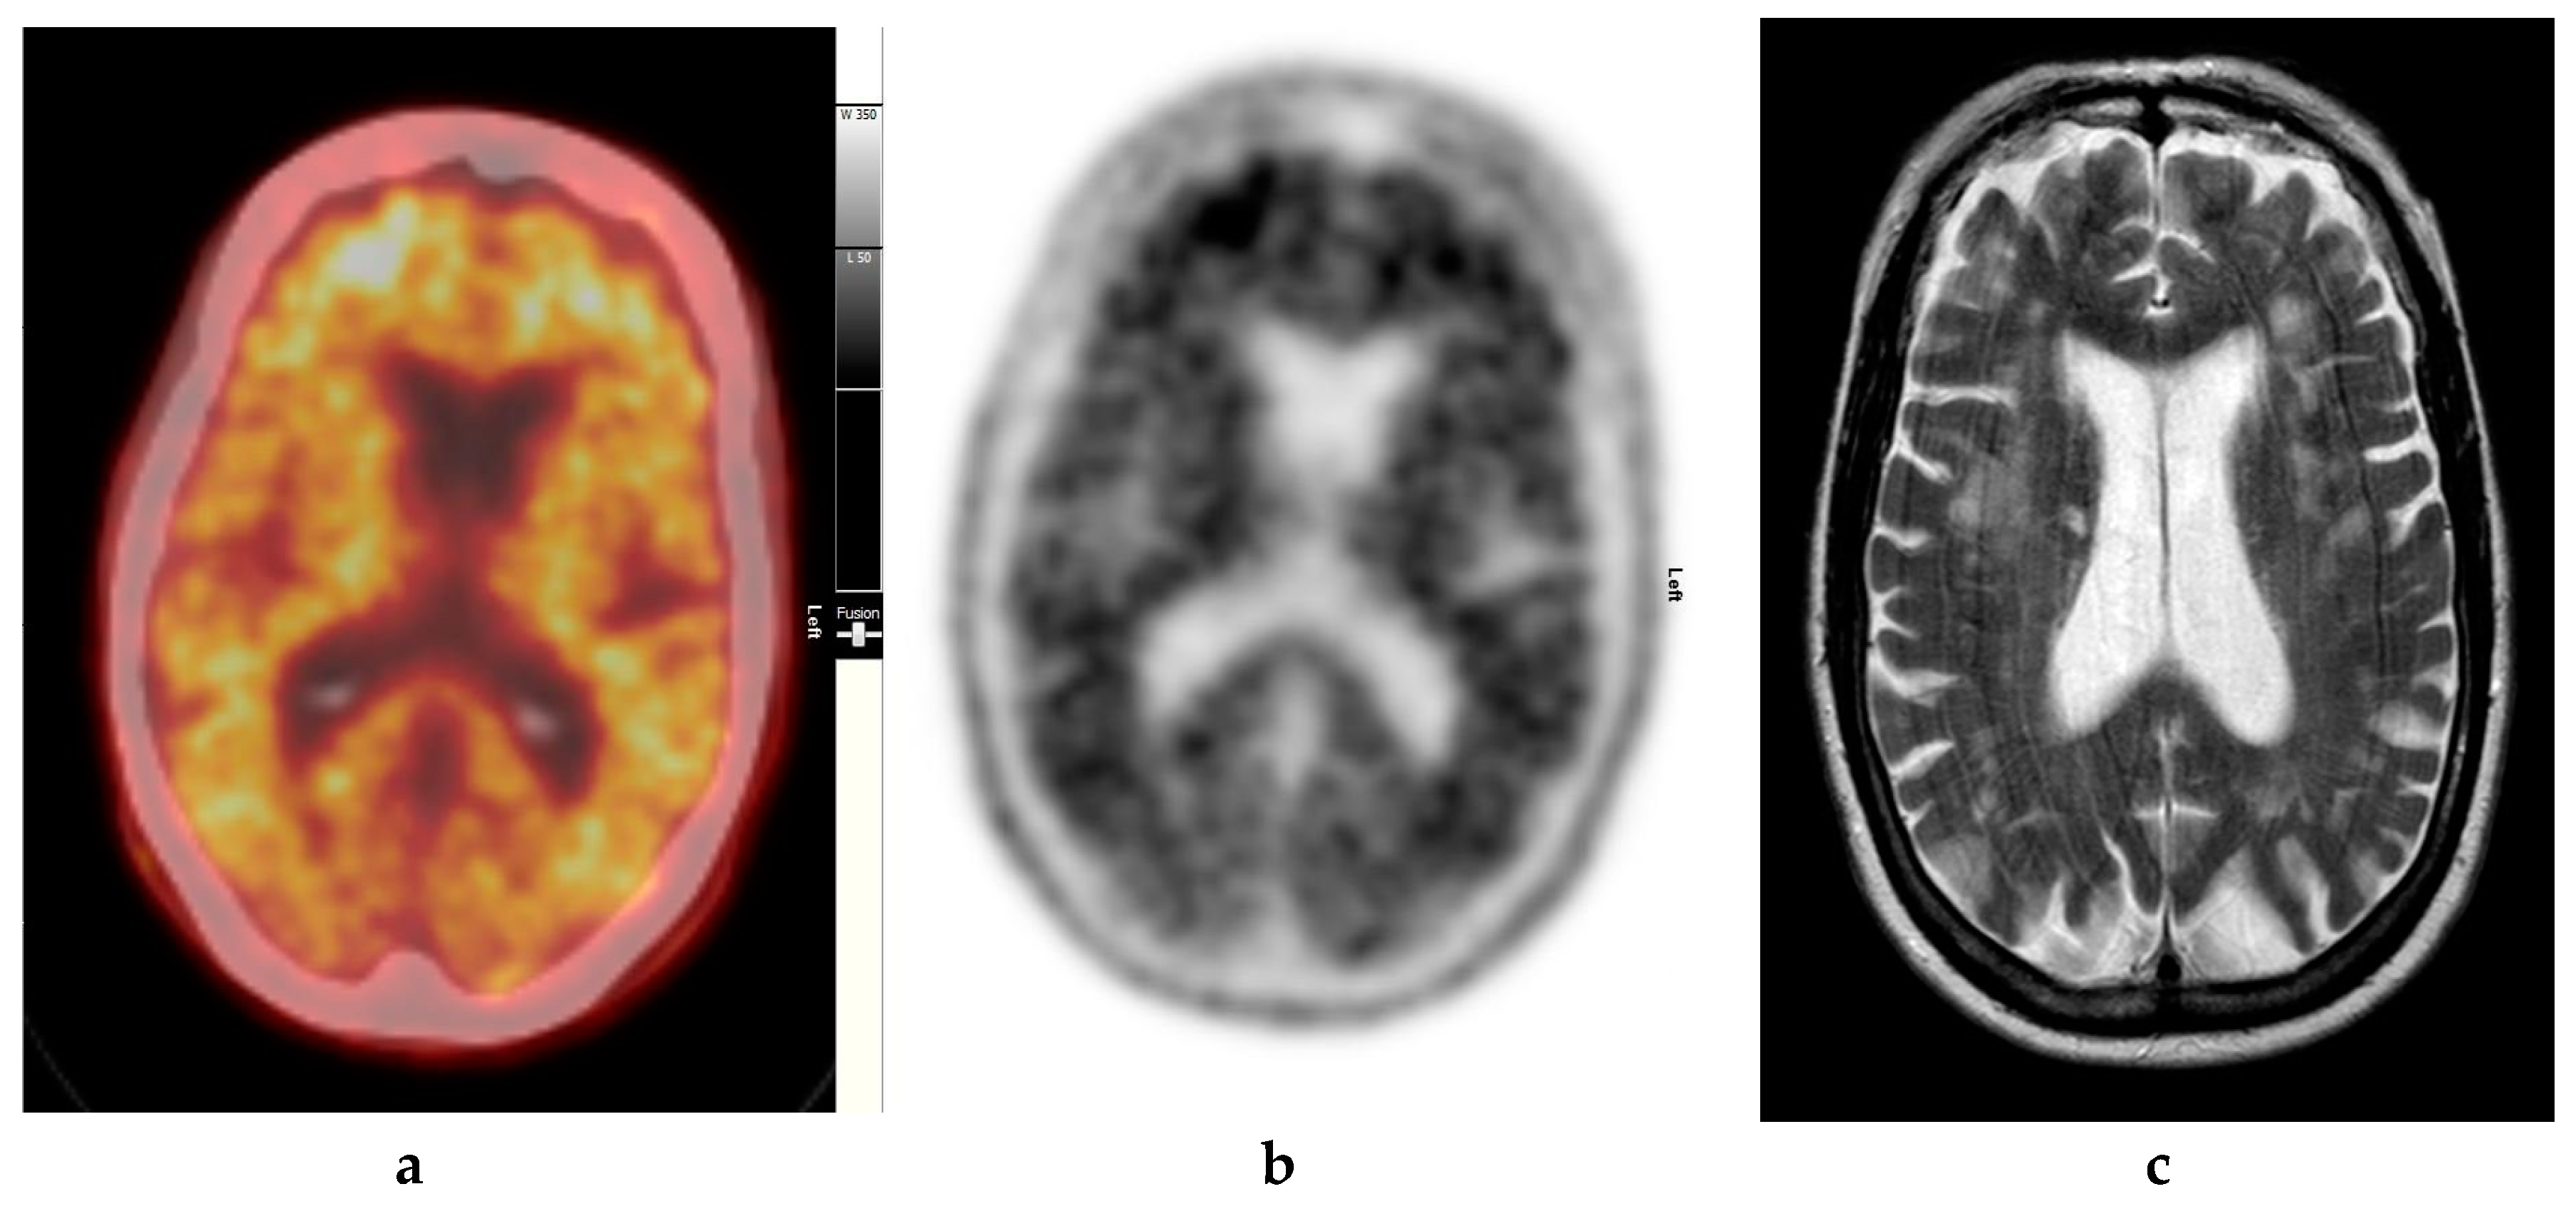

Figure 4.

Abnormal study. Sixty-eight year old female patient with speech difficulties, deficits in memory, and visuospatial abilities. (a) [99mTc]HMPAO-SPECT brain scan shows asymmetrical heterogenous reduced perfusion to both parietal and temporal lobes (worse on the left side) as with involvement of the frontal lobes identified by the yellow arrows. Normal areas of temporal perfusion were noted in between the abnormal parietal and frontal areas. In a patient with cognitive impairment, the findings indicate patterns of cerebral blood flow commonly seen in patients with mixed dementia, i.e., Alzheimer’s disease with vascular dementia. (b) Color coded [18F]FBP scan. (c) Grey scale [18F]FBP scans show loss of contrast between grey and white matter in all sections of the brain suggestive of beta-amyloid plaque deposition/disease. In conjunction with the [99mTc]HMPAO-SPECT brain scan, the overall findings are again suggestive of vascular as well as beta amyloid plaque disease (early AD), making the diagnosis mixed type AD. (Figures are courtesy RLBUHT Hospital database).